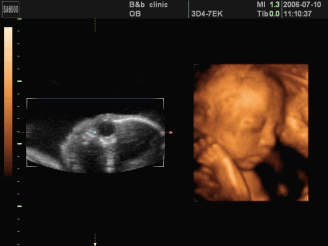

什么是四维彩超

四维彩超就像摄像机拍摄的VCR,在三维B超的基础上加上了时间轴,就像是摄像机所拍摄到的画面,是动态的宝宝。所以才会出现人们所说的可以看到胎儿在体内打哈欠的全过程的情况。

三维彩超、四维彩超的图像则是后期生成的,并不是说观察到的图像就是三维、四维的,而是仍然用普通彩超观察,然后通过仪器中的转换软件将观察到的平面图像转成三维、四维的立体图像。